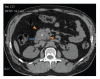

Paragangliomas are extra-adrenal tumors of the autonomic nervous system and may be found within the skull base, neck, chest, and abdomen. When presenting within the abdominal cavity, they may arise as a primary retroperitoneal neoplasm and can mimic vascular malformations or other conditions related to specific retroperitoneal organs such as the pancreas, kidneys, or adrenals. Retroperitoneal paragangliomas are mostly benign with good prognosis; however, they can present with abdominal pain, palpable mass, or hypertensive episodes. Patients should be initially evaluated with catecholamine levels, followed by computed tomography or magnetic resonance imaging to locate the primary lesion. Surgical excision remains the mainstay of treatment, although advanced disease and proximity to vital organs can make excision difficult or impossible. This case report describes a patient who initially underwent work up for a suspected pancreatic head mass which was discovered to be a retroperitoneal paraganglioma by frozen section.